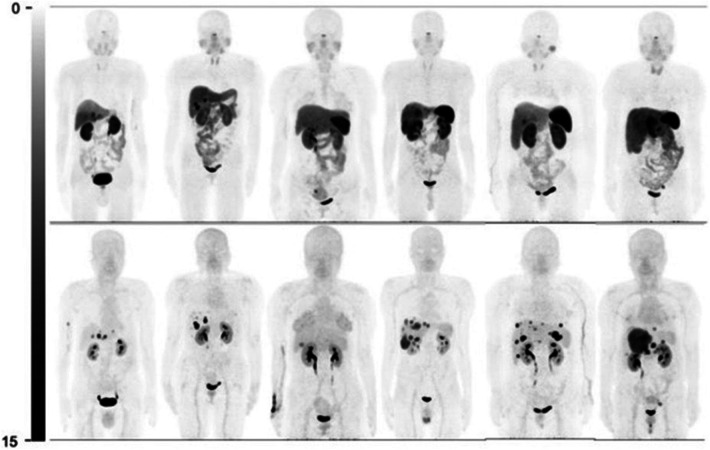

神经内分泌肿瘤(NETs)是一类异质性肿瘤,其特征是生长抑素受体(SSTRs)过表达,可用于肽受体放射性核素治疗。本文综述了自2020年以来放射性标记的sstr靶向放射性药物的临床试验的全面更新,重点是用68Ga、18F、99mTc、177Lu、161Tb、212Pb、67Cu和225Ac放射性标记的生长抑素受体激动剂和拮抗剂。头对头临床试验表明,与[68Ga]Ga-DOTA-TOC和[64Cu]Cu-DOTA-TATE等放射标记的激动剂相比,[68Ga]Ga-DOTA-JR11和[68Ga]Ga-DOTA-LM3等放射标记的SSTR拮抗剂提供了更好的病变检测和肿瘤-背景比(特别是在肝转移中)。此外,18F标记的药物比68Ga具有物流和剂量学方面的优势,因为18F的半衰期和回旋加速器生产时间更长,允许延迟成像,并增加了对更广泛患者的可用性。新出现的靶向α治疗药物,包括[225Ac]Ac-DOTA-TATE,由于α粒子的高线性能量转移,从而改善了局部细胞毒性,在治疗对常规疗法产生耐药性的疾病方面显示出有希望的结果。总的来说,这些发展支持向更精确、受体特异性治疗的转变,强调需要进一步进行面对面的临床试验,并在NETs管理中整合剂量学驱动的个性化治疗计划。

Neuroendocrine tumors (NETs) are a heterogeneous group of neoplasms characterized by their overexpression of somatostatin receptors (SSTRs), which can be utilized for peptide receptor radionuclide therapy. This review provides a comprehensive update on the clinical trials of radiolabeled SSTR-targeting radiopharmaceuticals since 2020, with a focus on somatostatin receptor agonists and antagonists radiolabeled with 68Ga, 18F, 99mTc, 177Lu, 161Tb, 212Pb, 67Cu, and 225Ac. Head-to-head clinical trials demonstrate that radiolabeled SSTR antagonists such as [68Ga]Ga-DOTA-JR11 and [68Ga]Ga-DOTA-LM3 offer improved lesion detection and tumor-to-background ratios (particularly in liver metastases) compared to radiolabeled agonists like [68Ga]Ga-DOTA-TOC and [64Cu]Cu-DOTA-TATE. Additionally, 18F-labeled agents offer logistical and dosimetric advantages over 68Ga, due to 18F's longer half-life and cyclotron production, allowing for delayed imaging and increased availability to a wider range of patients. Emerging targeted alpha therapy agents, including [225Ac]Ac-DOTA-TATE, show promising results in treating disease resistant to conventional therapies due to the high linear energy transfer of alpha particles, which leads to improved localized cytotoxicity. Collectively, these developments support a shift toward more precise, receptor-specific theragnostics, emphasizing the need for further head-to-head clinical trials and integration of dosimetry-driven, personalized treatment planning in the management of NETs.